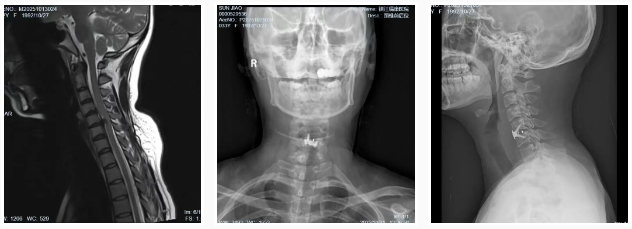

直到最近,情況急轉(zhuǎn)直下。她的左上肢開始出現(xiàn)持續(xù)性麻木,手指也變得不靈活,嚴(yán)重影響了工作和生活,甚至夜不能寐。門診收治入院后,經(jīng)過詳細(xì)檢查,診斷為“神經(jīng)根型頸椎病”,這意味著她的頸椎間盤已經(jīng)嚴(yán)重退化,壓迫到了神經(jīng)。如果不及時治療,可能會導(dǎo)致肢體癱瘓,后果不堪設(shè)想。孫女士最終接受了朱主任團(tuán)隊為其定制的頸椎前路顯微鏡下椎間盤切除融合術(shù)(ACDF),手術(shù)很成功,術(shù)后她的麻木感和疼痛都得到了明顯的緩解 。